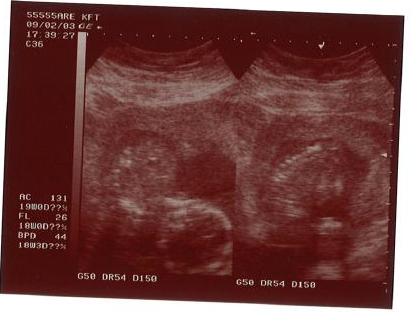

Sillia és Mini!!!! Örülök, hogy túl vagytok a vizsgálaton, megy a drukk-drukk!!!